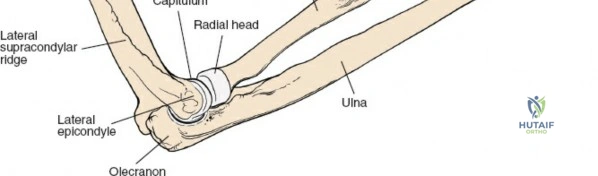

The radius and ulna function together as a highly coordinated articular quadrangle. The proximal radius consists of the radial head, which articulates with the capitellum; the radial neck; and the bicipital tuberosity, which serves as the insertion site for the biceps brachii tendon. The biomechanics of the forearm dictate that the radius rotates around the stationary ulna during pronation and supination. The normal lateral curvature of the radius—the radial bow—is critical for this rotational clearance. Any surgical approach to the proximal radius must allow for the precise restoration of this bow, as even a minor malreduction can lead to profound deficits in forearm rotation.

Landmarks and Incision Planning

Accurate identification of surface landmarks is the first step in a successful Henry approach. Palpate the biceps tendon, a stout, taut structure crossing the anterior elbow joint just medial to the brachioradialis muscle. Next, palpate the brachioradialis itself, the fleshy muscle forming the lateral border of the cubital fossa. Finally, identify the styloid process of the radius distally. Note that when the forearm is fully supinated (the anatomic position), the radial styloid is truly lateral.

Make a straight or gently curved incision beginning at the anterior flexor crease of the elbow, just lateral to the biceps tendon. Extend this incision distally toward the styloid process of the radius. The exact length and placement of the incision are dictated by the specific pathology; the approach is highly modular, and often only the proximal, middle, or distal third of the incision is required.